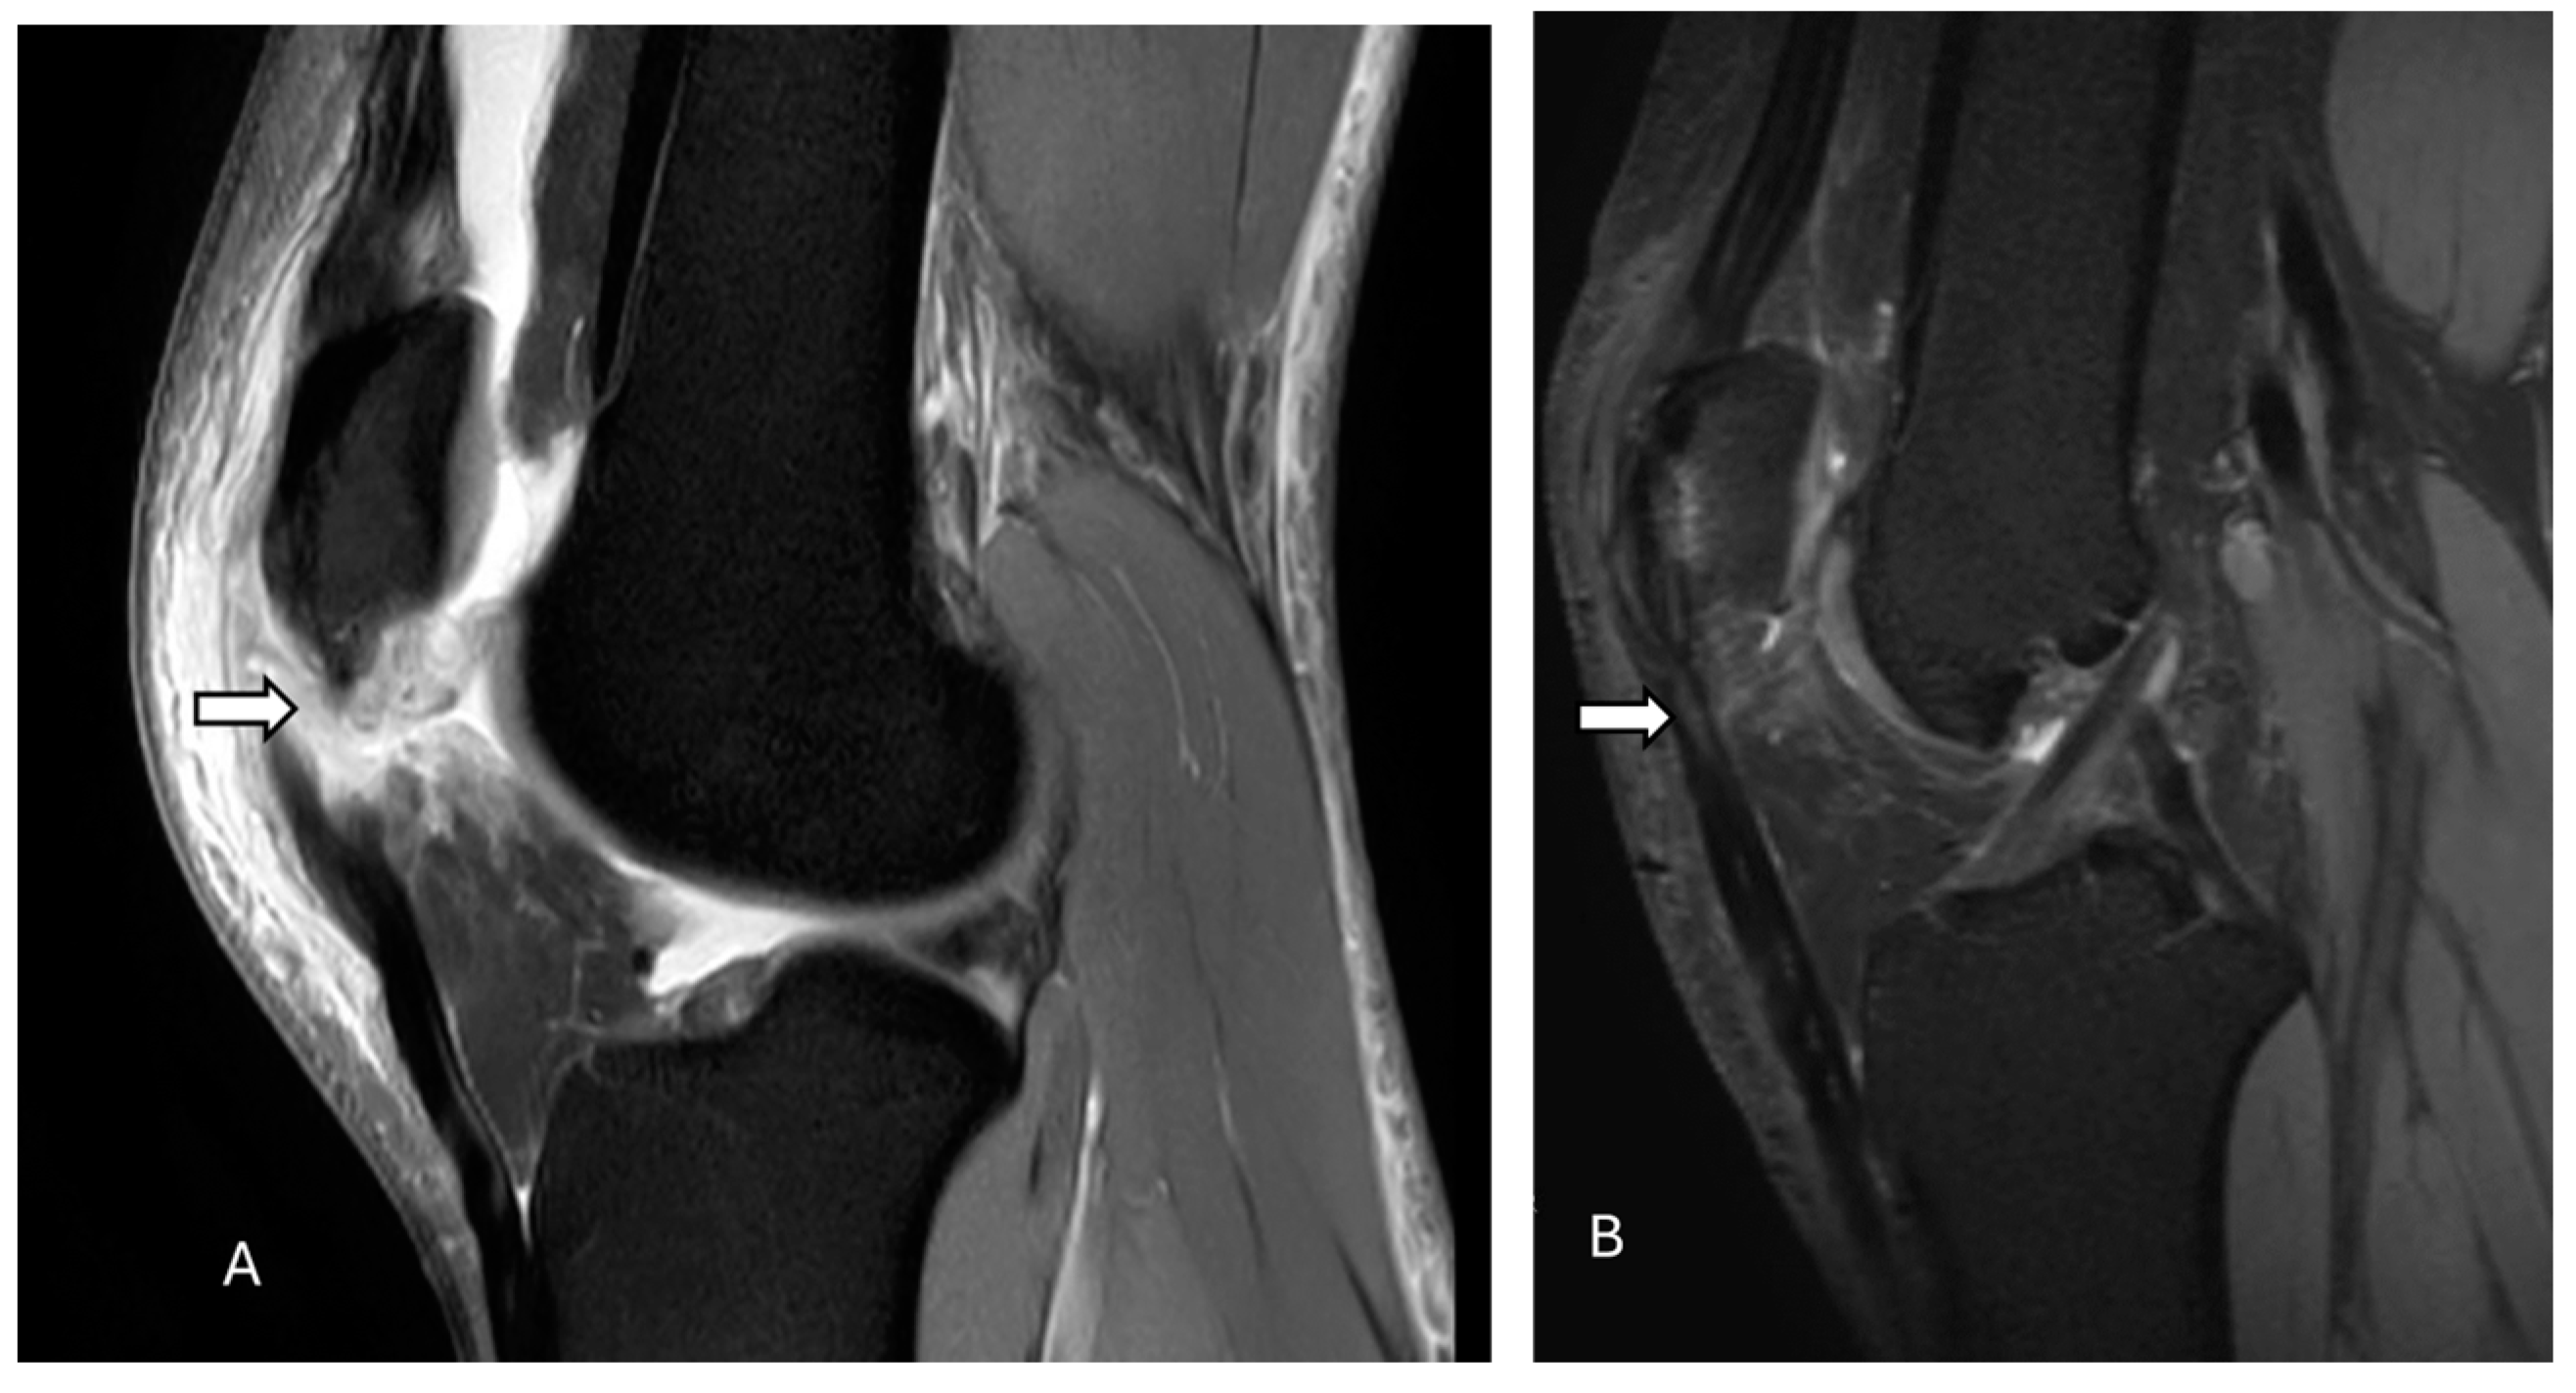

2.2. Dorsal Defect of the Patella